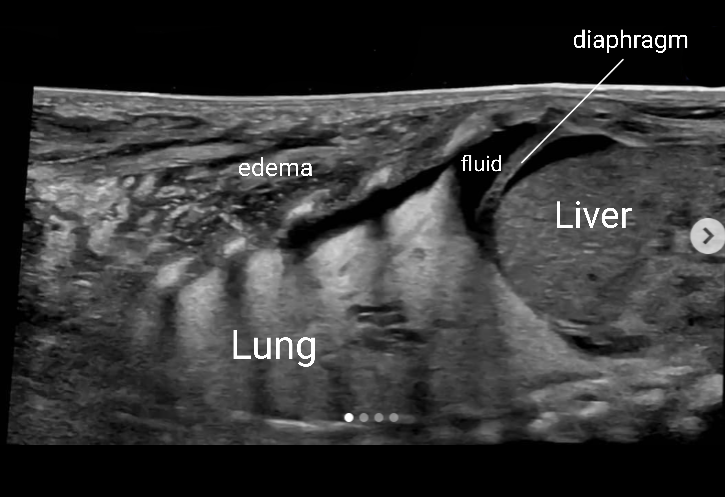

Pleural Effusion

Pleural effusion is a build up of fluid between the layers of the pleura. Scanning subcostally will show fluid above the diaphragm. Scanning intercostally will show fluid anterior the lung. Common causes for pleural effusion is infection, inflammation and malignancy.

The fluid can be anechoic or echogenic in cases of increased exudates, empyema, hemothorax and chylothorax (lymph collection). There may also be septations.

Pleural effusion can have transudative and exudative causes. Transudate is fluid pushed through the capillary due to high pressure within the capillary. Exudate is fluid that leaks around the cells of the capillaries caused by inflammation.